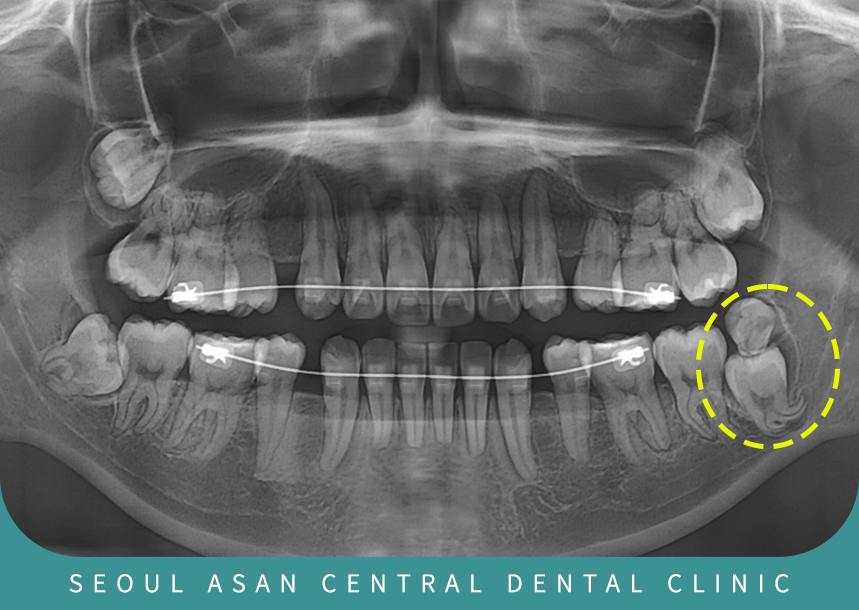

하악 좌측 부위에 매복된 사랑니와

과잉치가 인접 치아를 밀어내며

잇몸 염증과 반복적인 통증이 나타날 수 있는데요.

매복치 케이스의 경우는

하치조 신경관과 가까운 경우

발치 난이도가 어렵고,

복잡하기 때문에 성남치과에서는

우선 X-ray 촬영 및 CT 촬영을 진행하여

과잉치 상태를 확인하는 게 필요합니다.

사랑니와 함께 매복된 과잉치가 동시에 존재하는 경우,

인접한 제2대구치(어금니)를 밀어내어

치열을 흐트러뜨리거나 잇몸 염증,

통증 등의 문제를 유발할 수 있습니다.